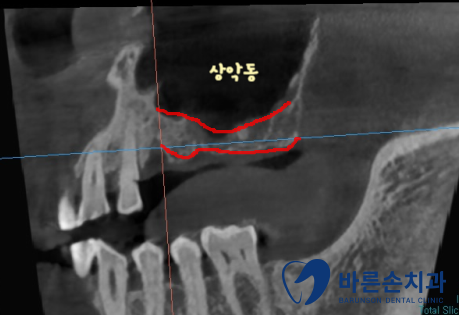

임플란트를 심기 위해서는 뼈가 충분히 있어야 하는데

상악동(빈 공간) 아래로 뼈가 너무 얇습니다.

상악동을 들어올려서 뼈이식을 충분히 하고 임플란트를 식립하기로 합니다.

이 수술 방법을 상악동 거상술이라고 해요.

좌우 모두 뼈를 만들면서 임플란트를 식립합니다.